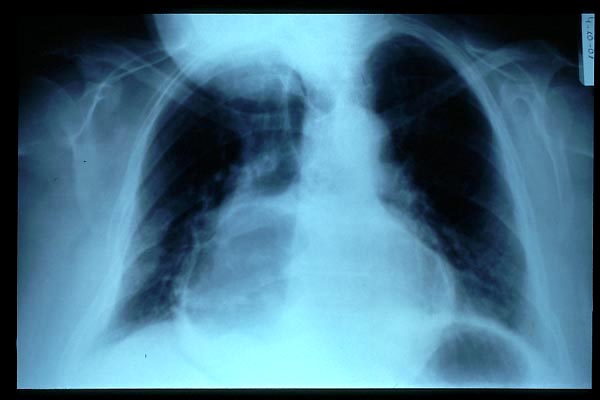

Fibrosis pulmonar. ICC.